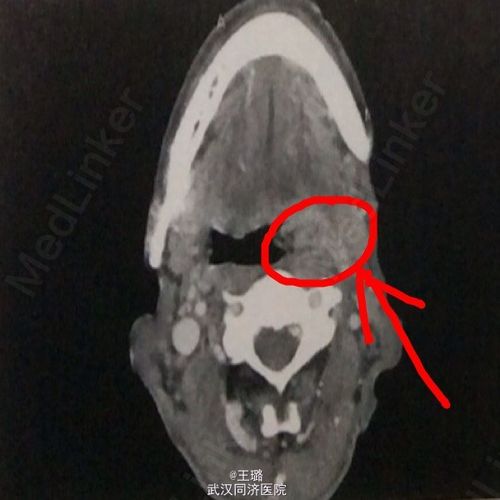

扁桃体癌照片,扁桃体癌早期

扁桃体癌一例

扁桃体癌早期

扁桃体癌图片

扁桃体癌早期图片